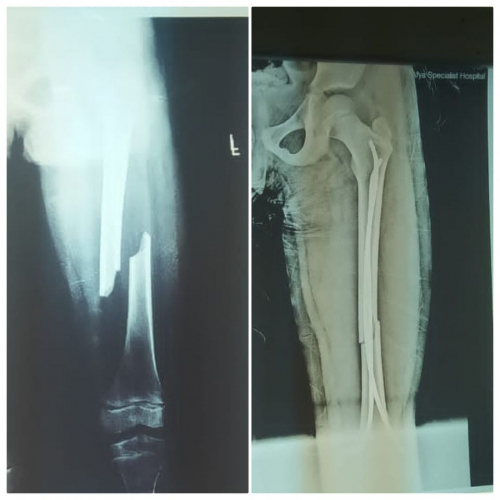

مشيرة أن طفلة في السابعة من عمرها تعرضت لكسر مضاعف في عظم الفخذ وتم نقلها إلى مستشفى عتق للأمومة والطفولة، حيث تقرر إجراء عملية جراحية مستعجلة وطلب أهل الطفلة أن يقوم بالعملية الدكتور محسن الشكليه، لكن إدارة المستشفى رفضت طلبهم ضمن سياستها في هو تهاون بأرواح المواطنين.